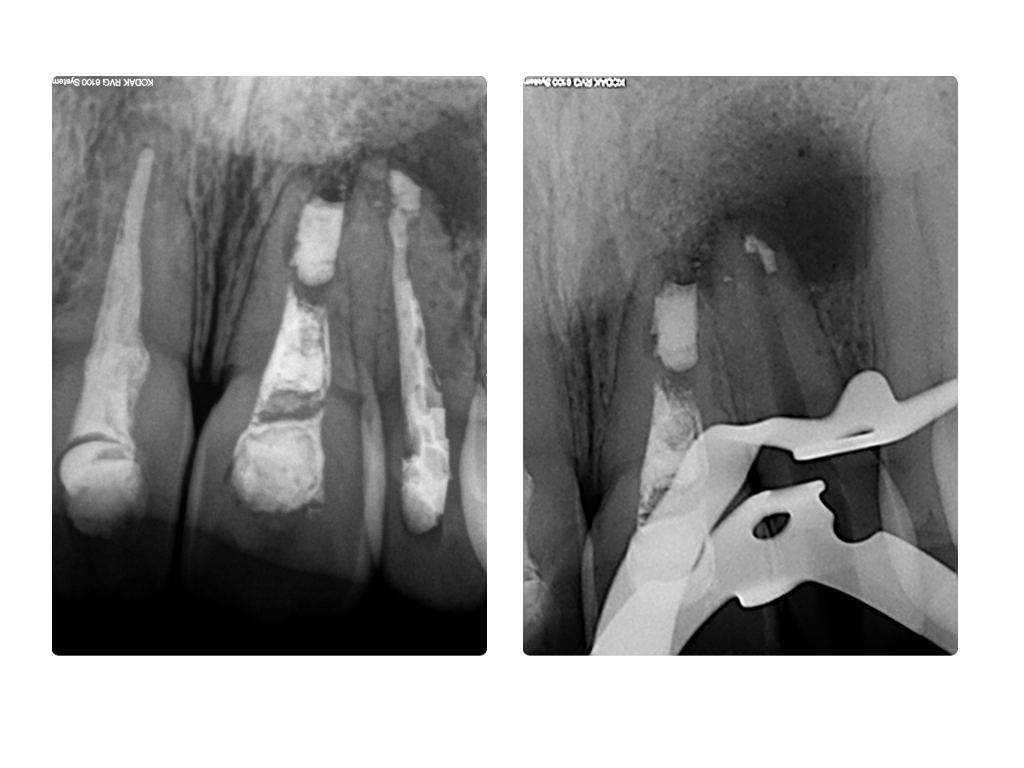

ws7.006 Veröffentlicht 27. Juni 2014 am 1024 × 768 in Einbahnstraße WSR (2) WF und retrograde WF Entfernung 22